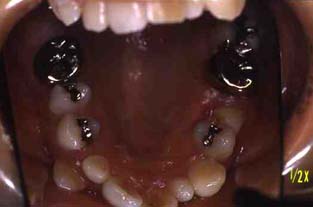

成人その3:八重歯と顎が狭い(唇側低位咬合,歯列狭窄) 22才,女性

矯正前

上顎

(ミラー像)